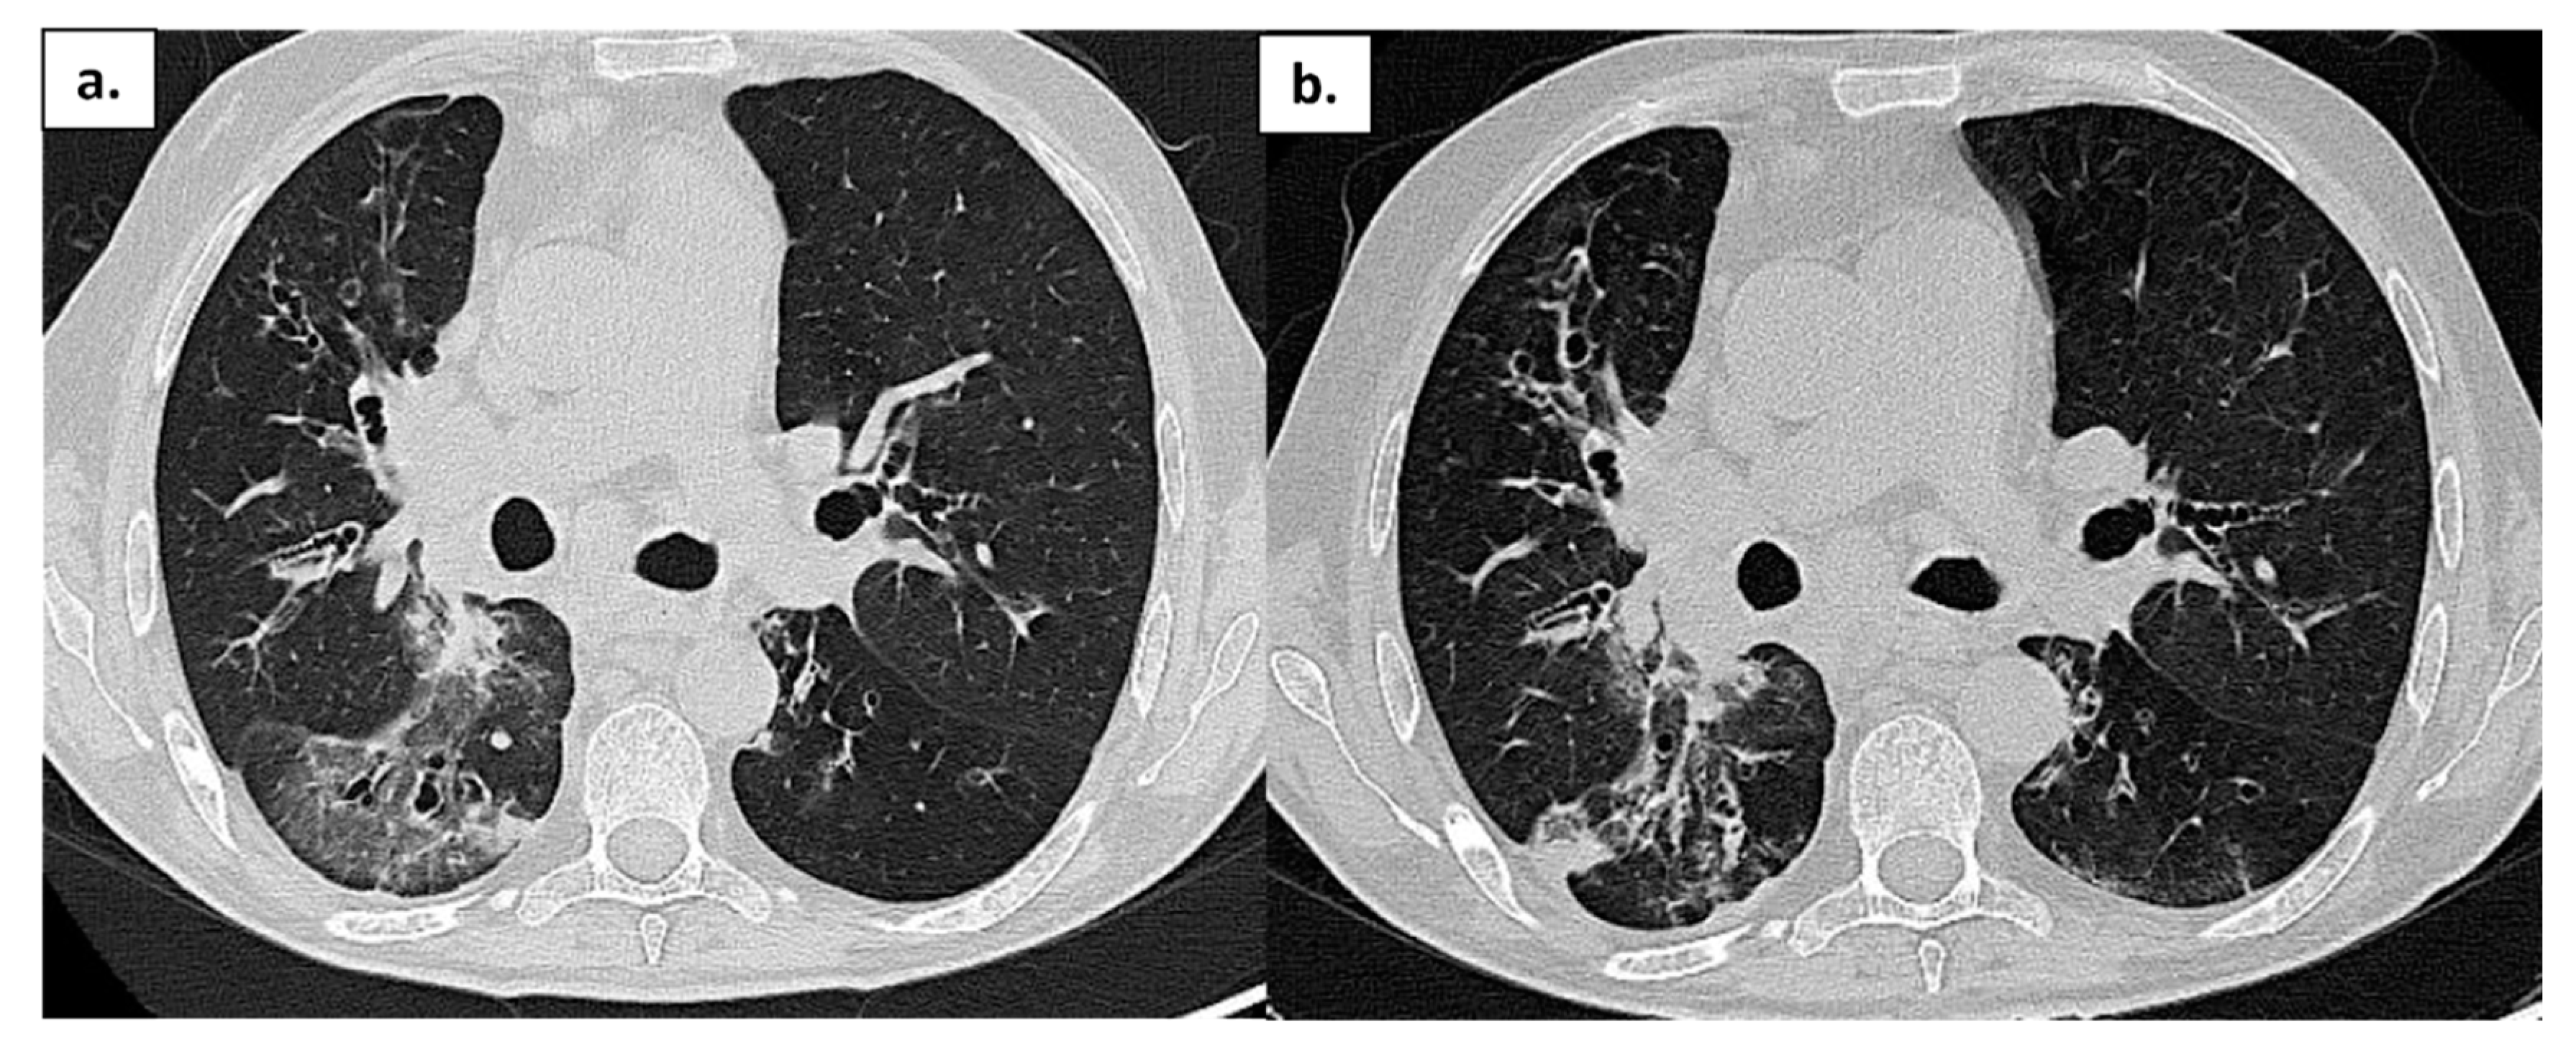

| Comorbidity | RA | Splenomegaly, bronchiectasis; recurrent viral infections | Hypertrophic cardiomyopathy; AF; CKD secondary to nephrolithiasis. C | Bronchiectasis; COPD; EBV-related NHL | GLILD; Bronchiectasis; colonization Aspergillus; Sjogren syndrome; CKD |

| SARS-CoV-2 related pneumonia | yes | yes | yes | yes | no |

| O2 supplementation therapy needed | LFNC | LFNC | HFNC | HFNC | LFNC |